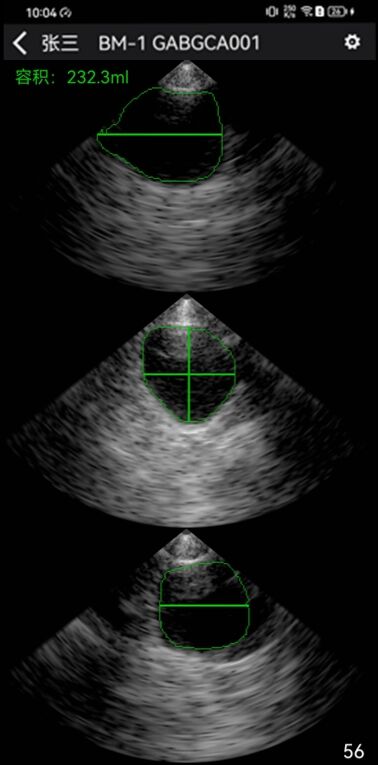

B1尿量监测器底部的三个多阵元相控阵探头,通过不同角度扫描膀胱并进行图像融合形成立体图像,计算出尿量。